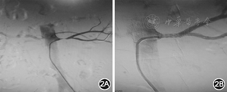

患者入院后低钠饮食,硝普钠持续静脉点滴控制血压。2014年6月26日患者过夜平卧10 h后平车送至数字减影血管造影(DSA)室,8:30血管介入科行双侧肾动脉造影及肾静脉采血,双侧肾动脉造影提示左侧肾动脉重度狭窄,程度约90%(图2A),因激素呈脉冲式分泌,双肾静脉及外周静脉分别采血2次,间隔5 min,结果见表1

左肾动脉支架植入术前(2A)及术后(2B)

结合之前所述左肾GFR明显降低及肾动脉造影结果,可见左肾动脉重度狭窄是导致本例恶性高血压、低血钾的病因。2014年6月30日行左肾动脉支架植入术(图2B)。术后30 min停用硝普钠,口服硝苯地平控释片30 mg/d,厄贝沙坦150 mg/d控制血压,血压控制在130~140/80~90 mmHg。术后3 d复查卧位外周静脉血肾素活性:2.74 ng·L–1·h–1,醛固酮100.8 ng/L;血钾3.54 mmol/L。出院时继续口服硝苯地平控释片30 mg/d,厄贝沙坦150 mg /d控制血压,胰岛素强化治疗控制血糖,阿托伐他汀钙40 mg/d调血脂,拜阿司匹林100 mg/d抗血小板。出院1个月后门诊复查血压130/80 mmHg;血钾4.07 mmol/L,肾功能正常,尿常规:蛋白质(+),隐血(±)。出院6个月门诊复查血压120/80 mmHg;血钾4.00 mmol/L,肾功能正常,尿常规:蛋白质(±),隐血阴性。